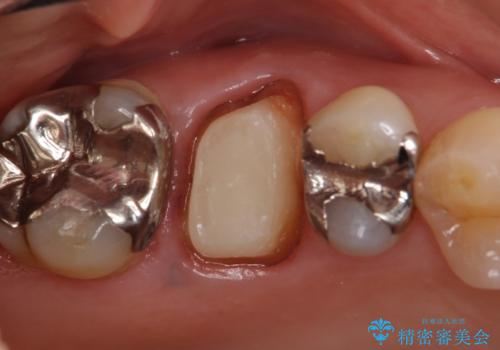

- 右上6番目の銀歯と歯茎の間に隙間ができているのが気になるので診て欲しいといらっしゃった方の症例です。

根管治療も希望されたため、再根管治療終了後、オールセラミッククラウンによる補綴を行いました。

今回用いたオールセラミッククラウンはジルコニアフレームという白い素材の上にセラミックを盛っているため、審美性が非常に高いのが特徴です。

また、ジルコニアは人工ダイヤモンドの材料にも使われているほど高い強度を持っており、そのためオールセラミッククラウンは審美性だけでなく、奥歯やブリッジの補綴も可能とするクラウンです。